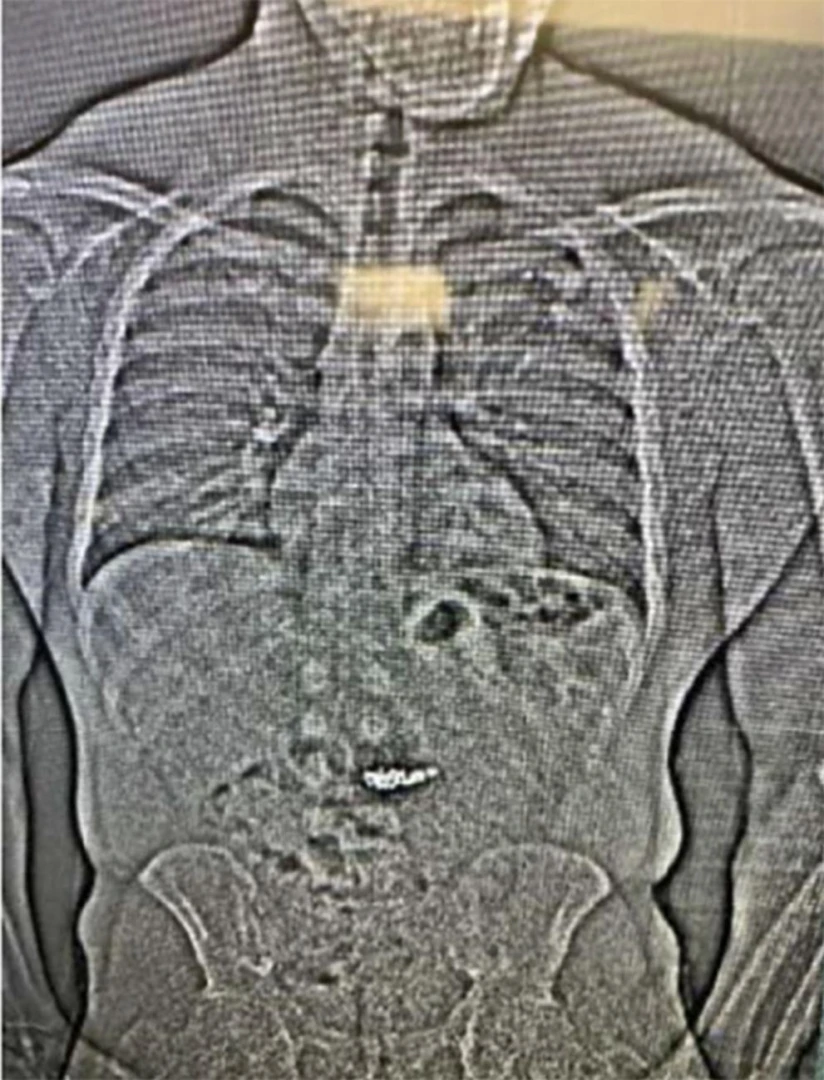

След направен скенер в затвора, властите открили липсващите бижута в стомаха му. „Тези чужди обекти вероятно са обеците от Tiffany & Co., но ще трябва да бъдат събрани след преминаването им през храносмилателната система на Гилдър“, се посочва в доклада.